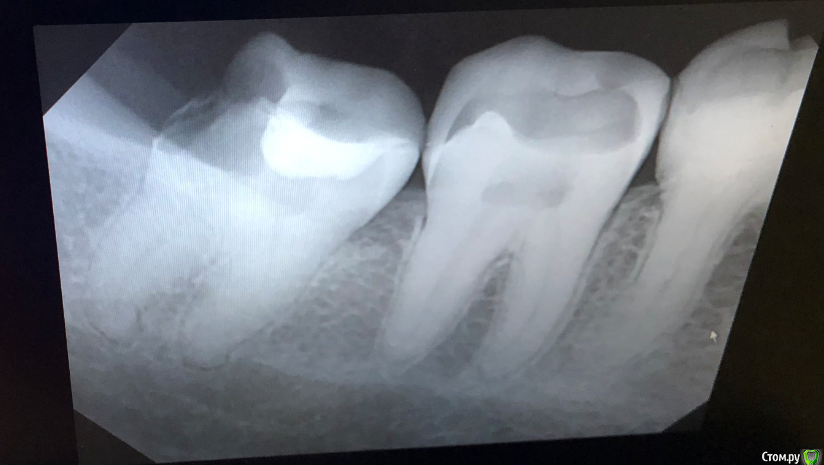

korkor Опубликовано 30 января, 2020 Поделиться Опубликовано 30 января, 2020 (изменено) Недавно заболел зуб. Болел после горячего. Потом просто стал болеть, даже проснулся ночью как-то от боли.Был у стоматолога. Она начала лечить зуб с одним каналом 29 (на фото он правее), так как там кариес был и дырка довольна большая. Рядом с ним 30 (левее) зуб мне лечили лет 10 назад. Сначала стоматолог говорила, что канал до конца недолечили, так как на снимке не видно, плюс инструмент в канале. Но так как у меня одна стенка зуба вся темно-коричневая (давно начал темнеть постепенно, сейчас весь темный), скорее всего там резицин-формалин. Рядом с ним зуб 31 (еще правее), сказала, что якобы может быть трещина в корню посередине зуба (на еще одном снимке там якобы темное уплотнение под корнем). И последний зуб мудрости (32) - там часть зуба откололась.Пролечили мне 29-й зуб с одним каналом. Но боль то есть, то нету. боль в основном ноющая, один день вообще ее нету, на другой опять есть, но слабее, чем была. 1. Помогите разобраться какой зуб может болеть и ответить на вопрос правильно ли мне удалили нерв в 29-м зубе?2. Возможно ли запломбировать 32-й зуб, коренной без удаления нерва? И если нельзя, то что лучше - удалять зуб или прочистить каналы и запломбировать?3. Что посоветуете делать с 30-м зубом (коричневый) и возможна ли боль от трещины (и есть ли трещина) в 31-м зубе? Изменено 30 января, 2020 пользователем korkor Ссылка на комментарий